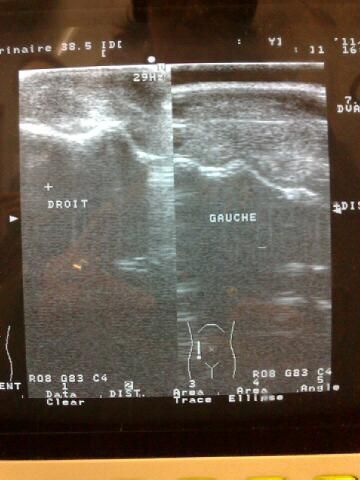

DéconnectéDire merci | Les radio et l'echographie montre un diminution de l'épaisseur du cartilage, mais elle ne sont pas très explicites. ![]() le cote gauche est le cote endomagé. On voit un une ligne blanche qui se pert un peu |